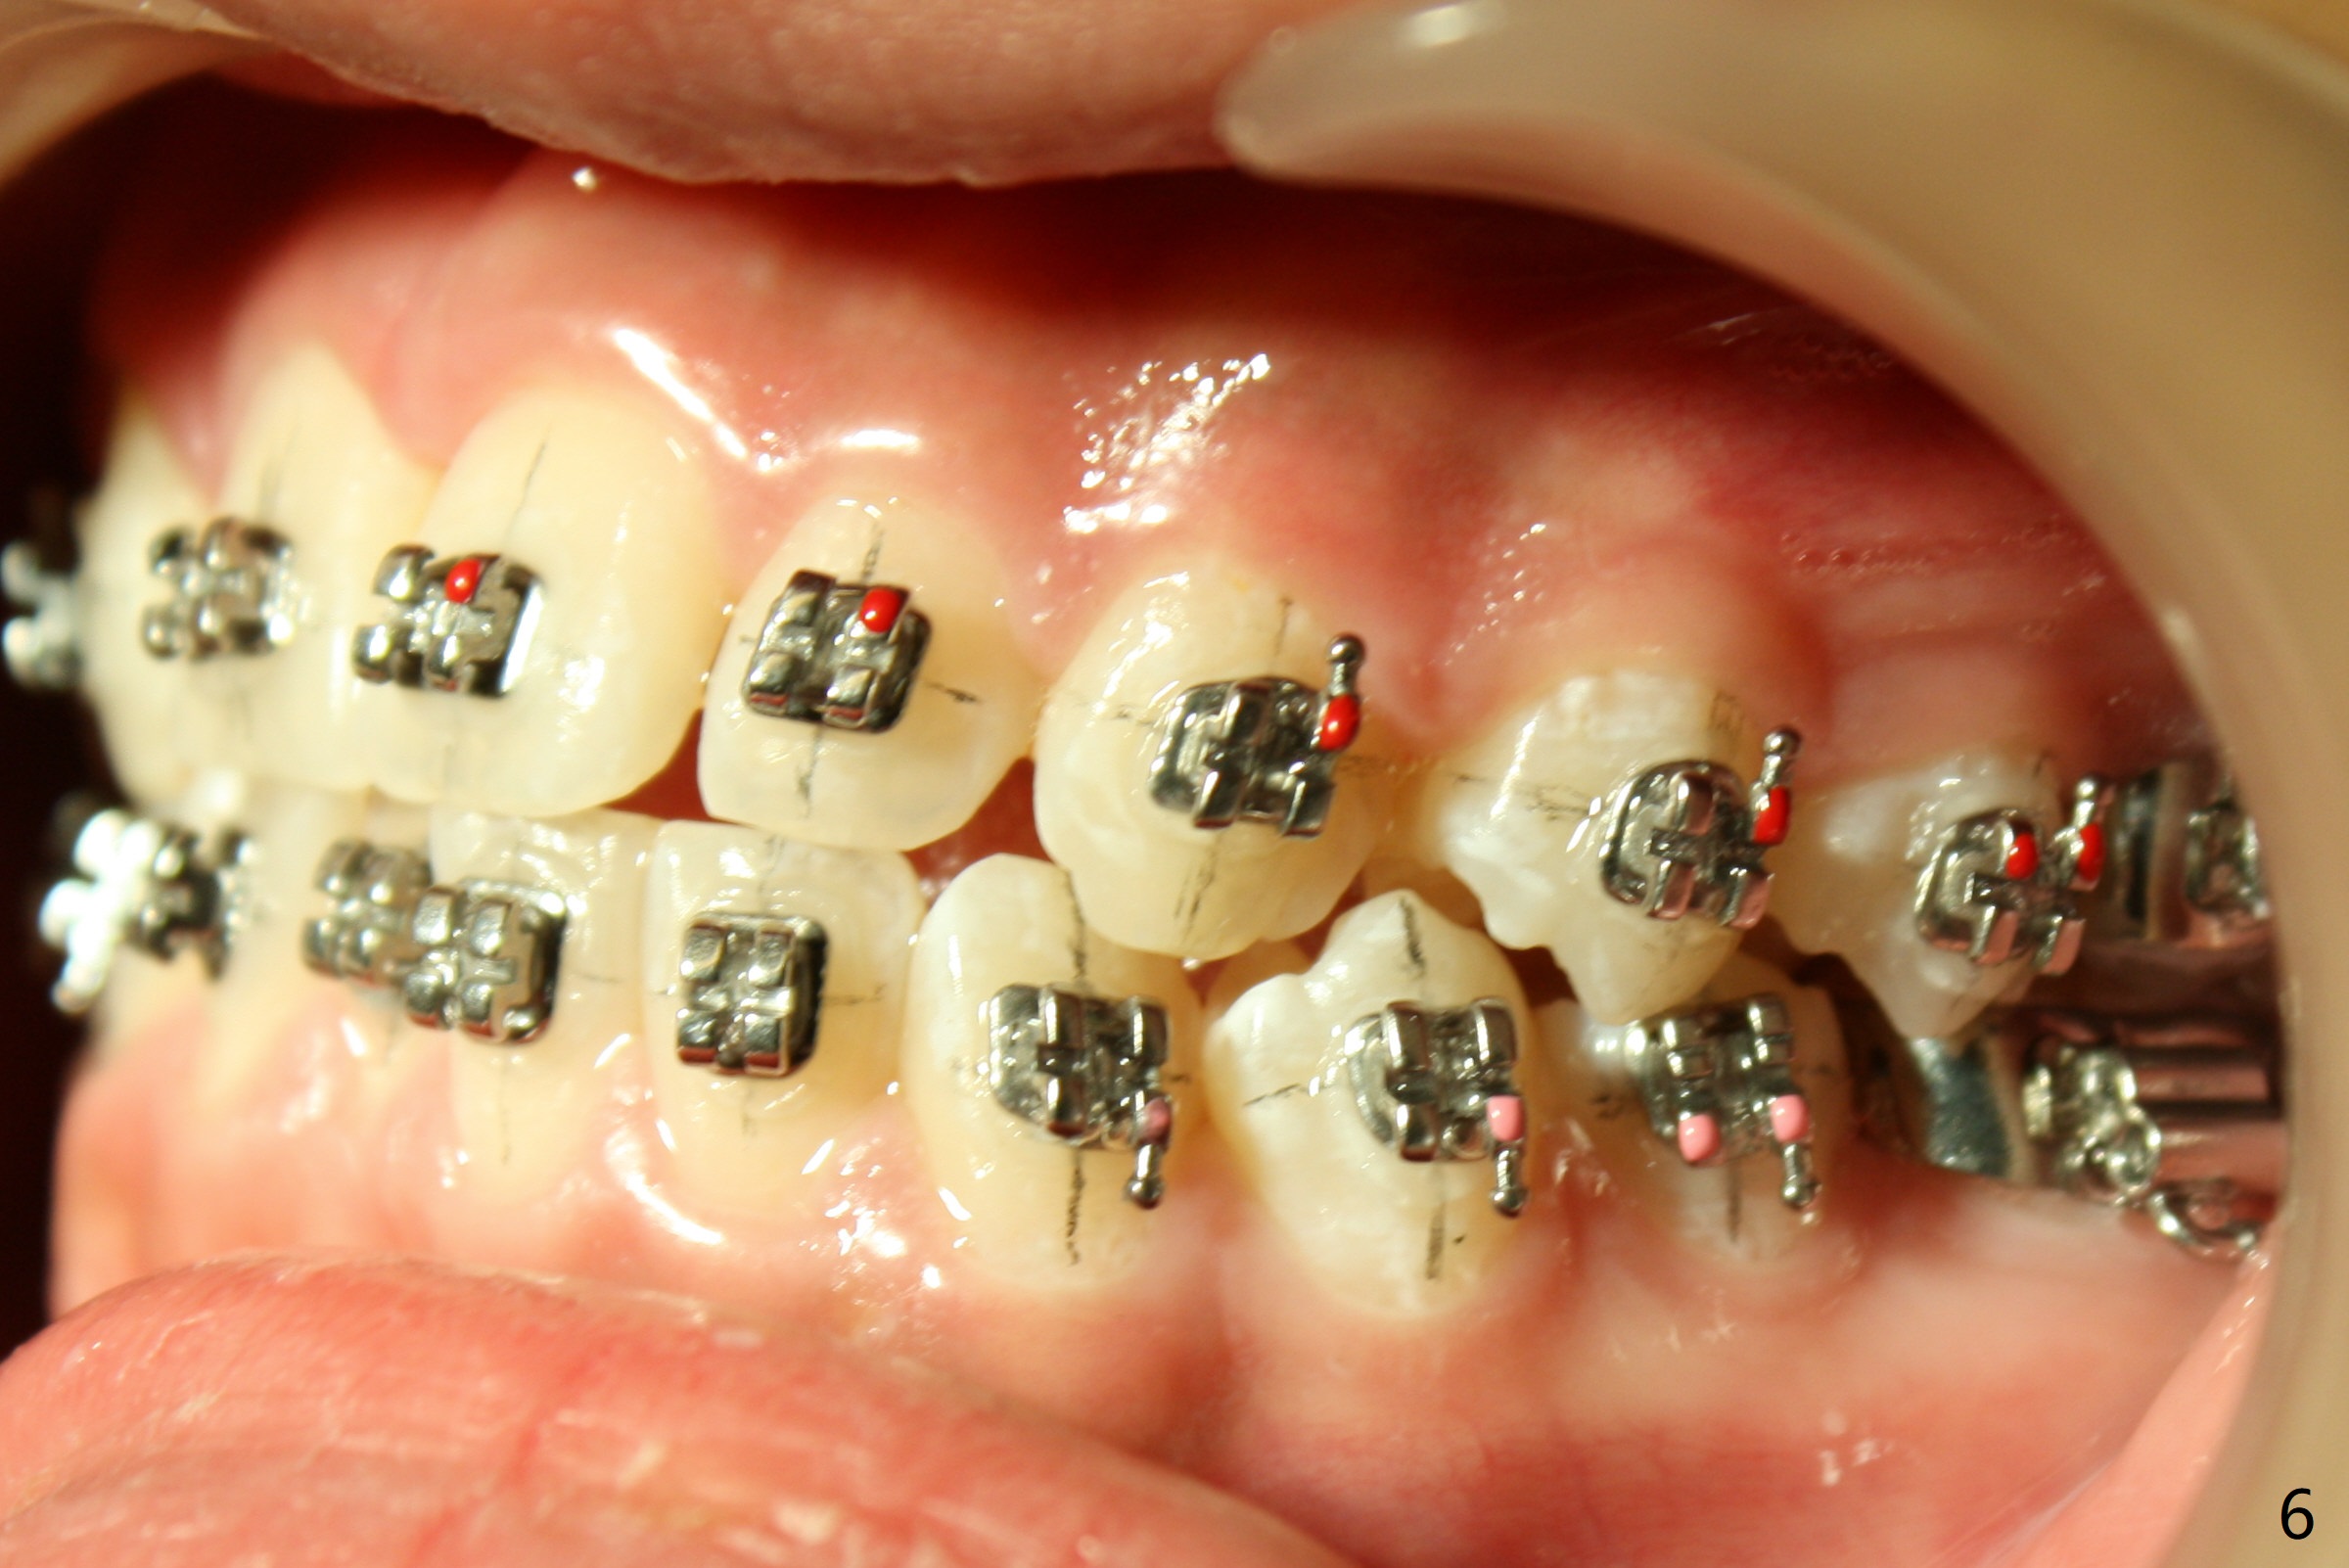

Preop cephalometric tracing shows normal skeletal relationship (Fig.1,2). The upper dental midline deviates to the right (Fig.3). To control root torque, UR1,3 bracketing is intentionally placed off (Fig.4,5, as compared to Fig.6). Take PA for UR1/3 next visit. In fact PA has not been taken. The patient has complained of UR1 turning (mesial incisal edge elongation due to bracket off placement) since the 1st appointment post banding. On the 3rd appointment (2 months 12 days post banding with 18 ss wire), the mesial incisal edge of UR1 and the distal incisal edge of UR3 are trimmed; 18 wires are reused with addition of an open coil spring between UR1-3 (Fig.7). Extra diastemata have appeared mesial and distal to UL1 (Fig.8 *), creating room to correct the upper dental midline shifting. PA is taken 5 months post banding (Fig.9). The roots of neighboring teeth are parallel with new bone formation behind. The mesiodistal space is similar to that of the tooth #10 following consolidation of diastemata on the left. More space is gained 12 months post banding (Fig.10).